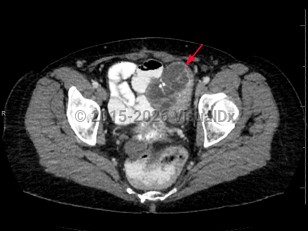

Rectal carcinomaRectal carcinoma

Metastatic pancreatic carcinomaMetastatic pancreatic carcinoma